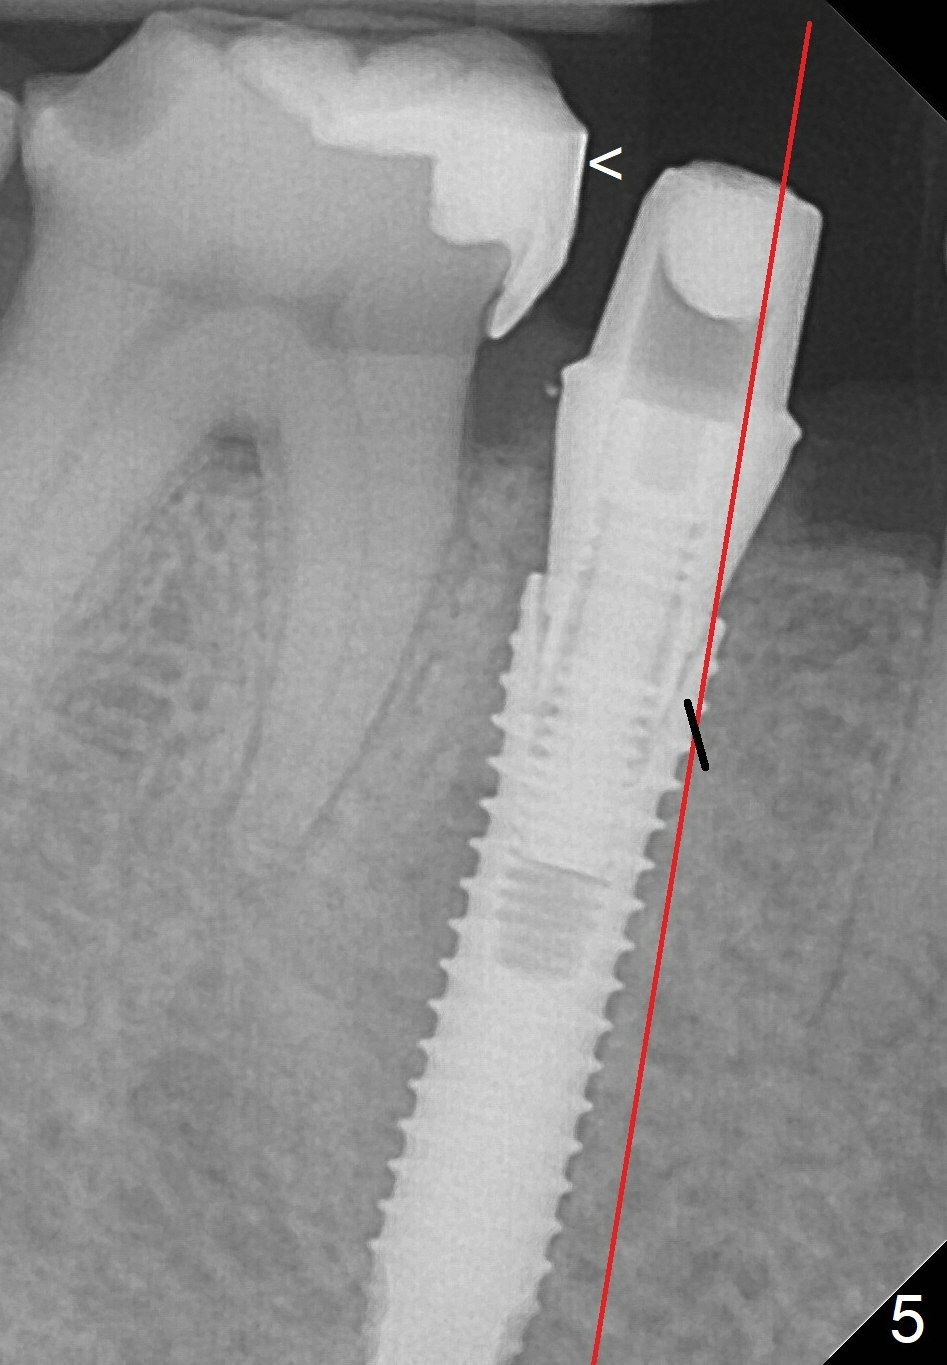

A 67-year-old woman fractures the tooth #29 three months post RCT. There is persistent periapical radio-lucency (Fig.1 yellow dashed line), which is close to the Mental Loop (red dashed line). Since the root of the affected tooth deviates distal, osteotomy will be established mesial (Fig.2). In fact it is not so easily accomplished; the osteotomy is initiated as mesial as possible (Fig.3 (yellow dashed line: original socket)). When a 3.8x16 mm implant is being placed, it is distal (Fig.4). The MO composite of the tooth #30 has to be trimmed for fabrication of an immediate provisional (Fig.5 <).

To place the implant mesially, the initial osteotomy should be established higher in the mesial slope of the socket (Fig.3 red line). Once the drill penetrates the lamina dura (Fig.5 short black line), change the trajectory (Fig.5 red line). A potential drawback may be loss of primary stability when osteotomy increases.